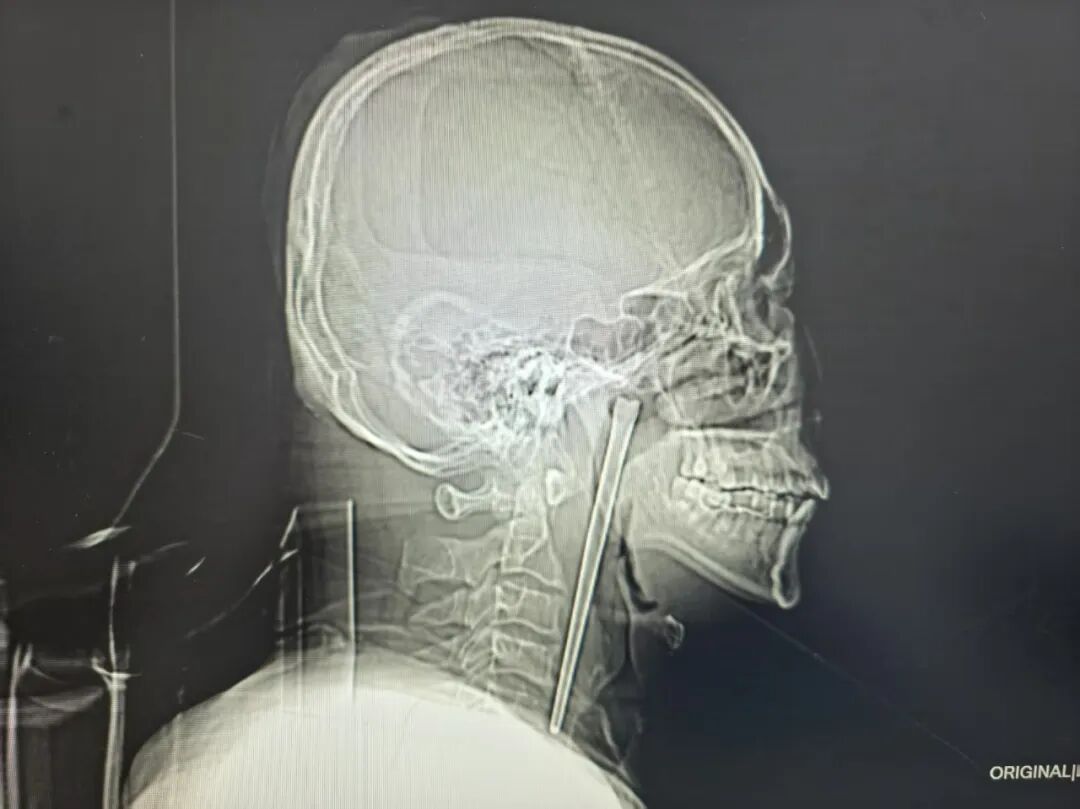

According to local media reports, the man, surnamed Wang, had swallowed a 12cm-long metal chopstick by accident while eating.

Upon rushing to the hospital, doctors found that the chopstick was embedded in the back of his throat, with about 3cm of it protruding at the top.

A minimally invasive operation was then carried out to extract the chopstick from Wang’s mouth without having to cut his neck, finally freeing him from the object.